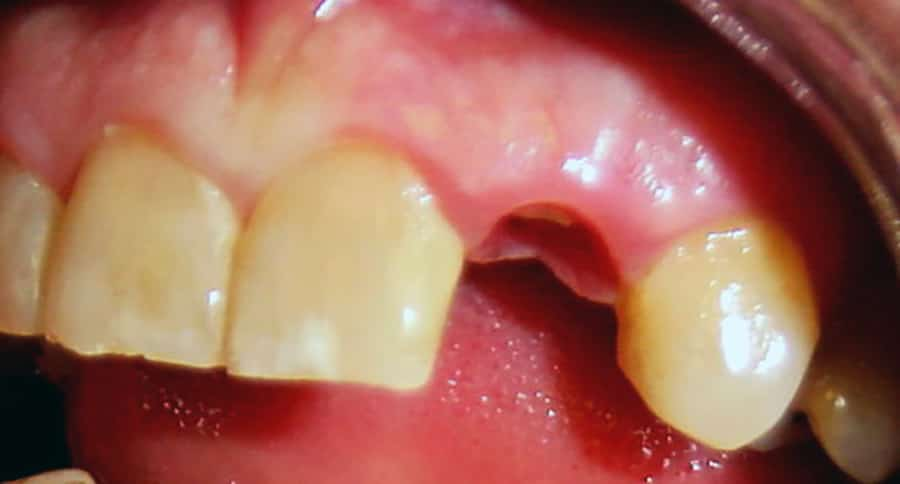

Impianto

Prima / Dopo